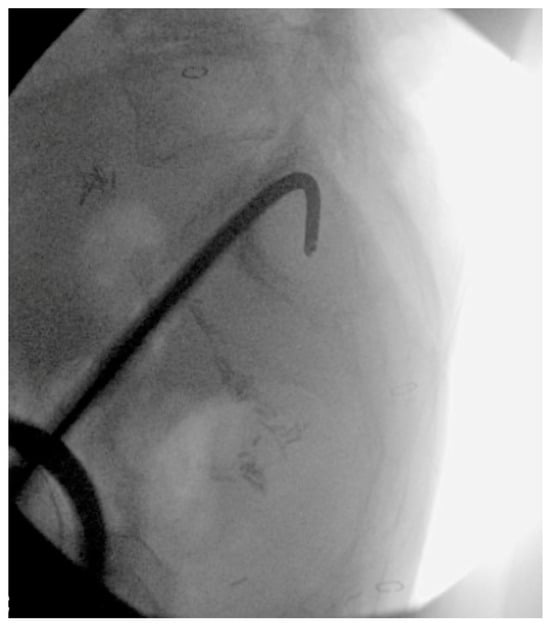

6. Spinopelvic Fixation Percutaneous Technique

7. Tran-Sacral Percutaneous Technique